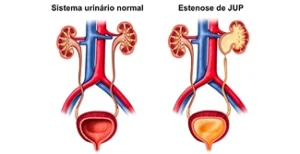

Condição em que há obstrução entre a pelve renal e o ureter, levando à dilatação do rim. O tratamento cirúrgico visa restaurar o fluxo urinário normal.

Procedimento de escolha para correção da estenose de JUP, utilizando tecnologia robótica para reconstruir a junção ureteropiélica com precisão e resultados duradouros.